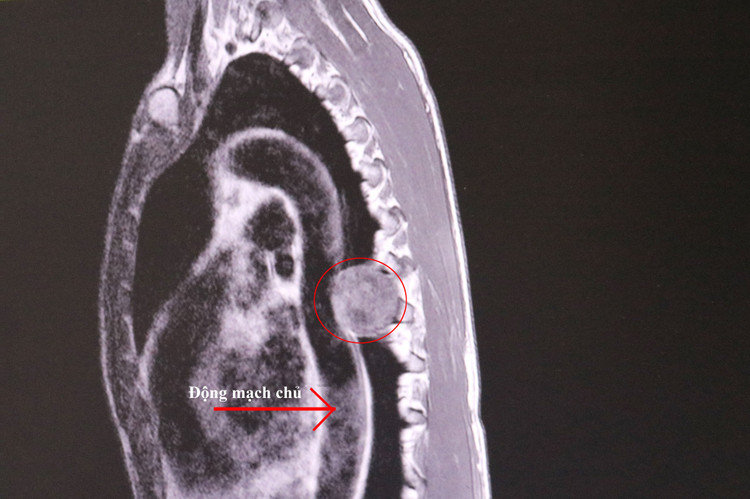

Khối u nằm ngang đốt sống ngực số 7 (D7), 1 phần khối u chèn ép vào tuỷ sống, 1 phần khối u nằm trong trung thất sau của người bệnh.

Các bác sĩ Khoa Ngoại thần kinh đã phải cắt một phần cung sau đốt sống D7 để tiếp cận khối u, cắt bỏ phần khối u chèn ép tại tuỷ sống. Sau đó các bác sĩ Khoa phẫu thuật can thiệp tim mạch - lồng ngực tiến hành nội soi khoang màng phổi trái cắt phần khối u nằm trong trung thất sau chèn ép vào màng phổi và động mạch chủ ngực xuống.

| Khối u trung thất lớn chèn ép tủy trên phim chụp - Ảnh BVCC |